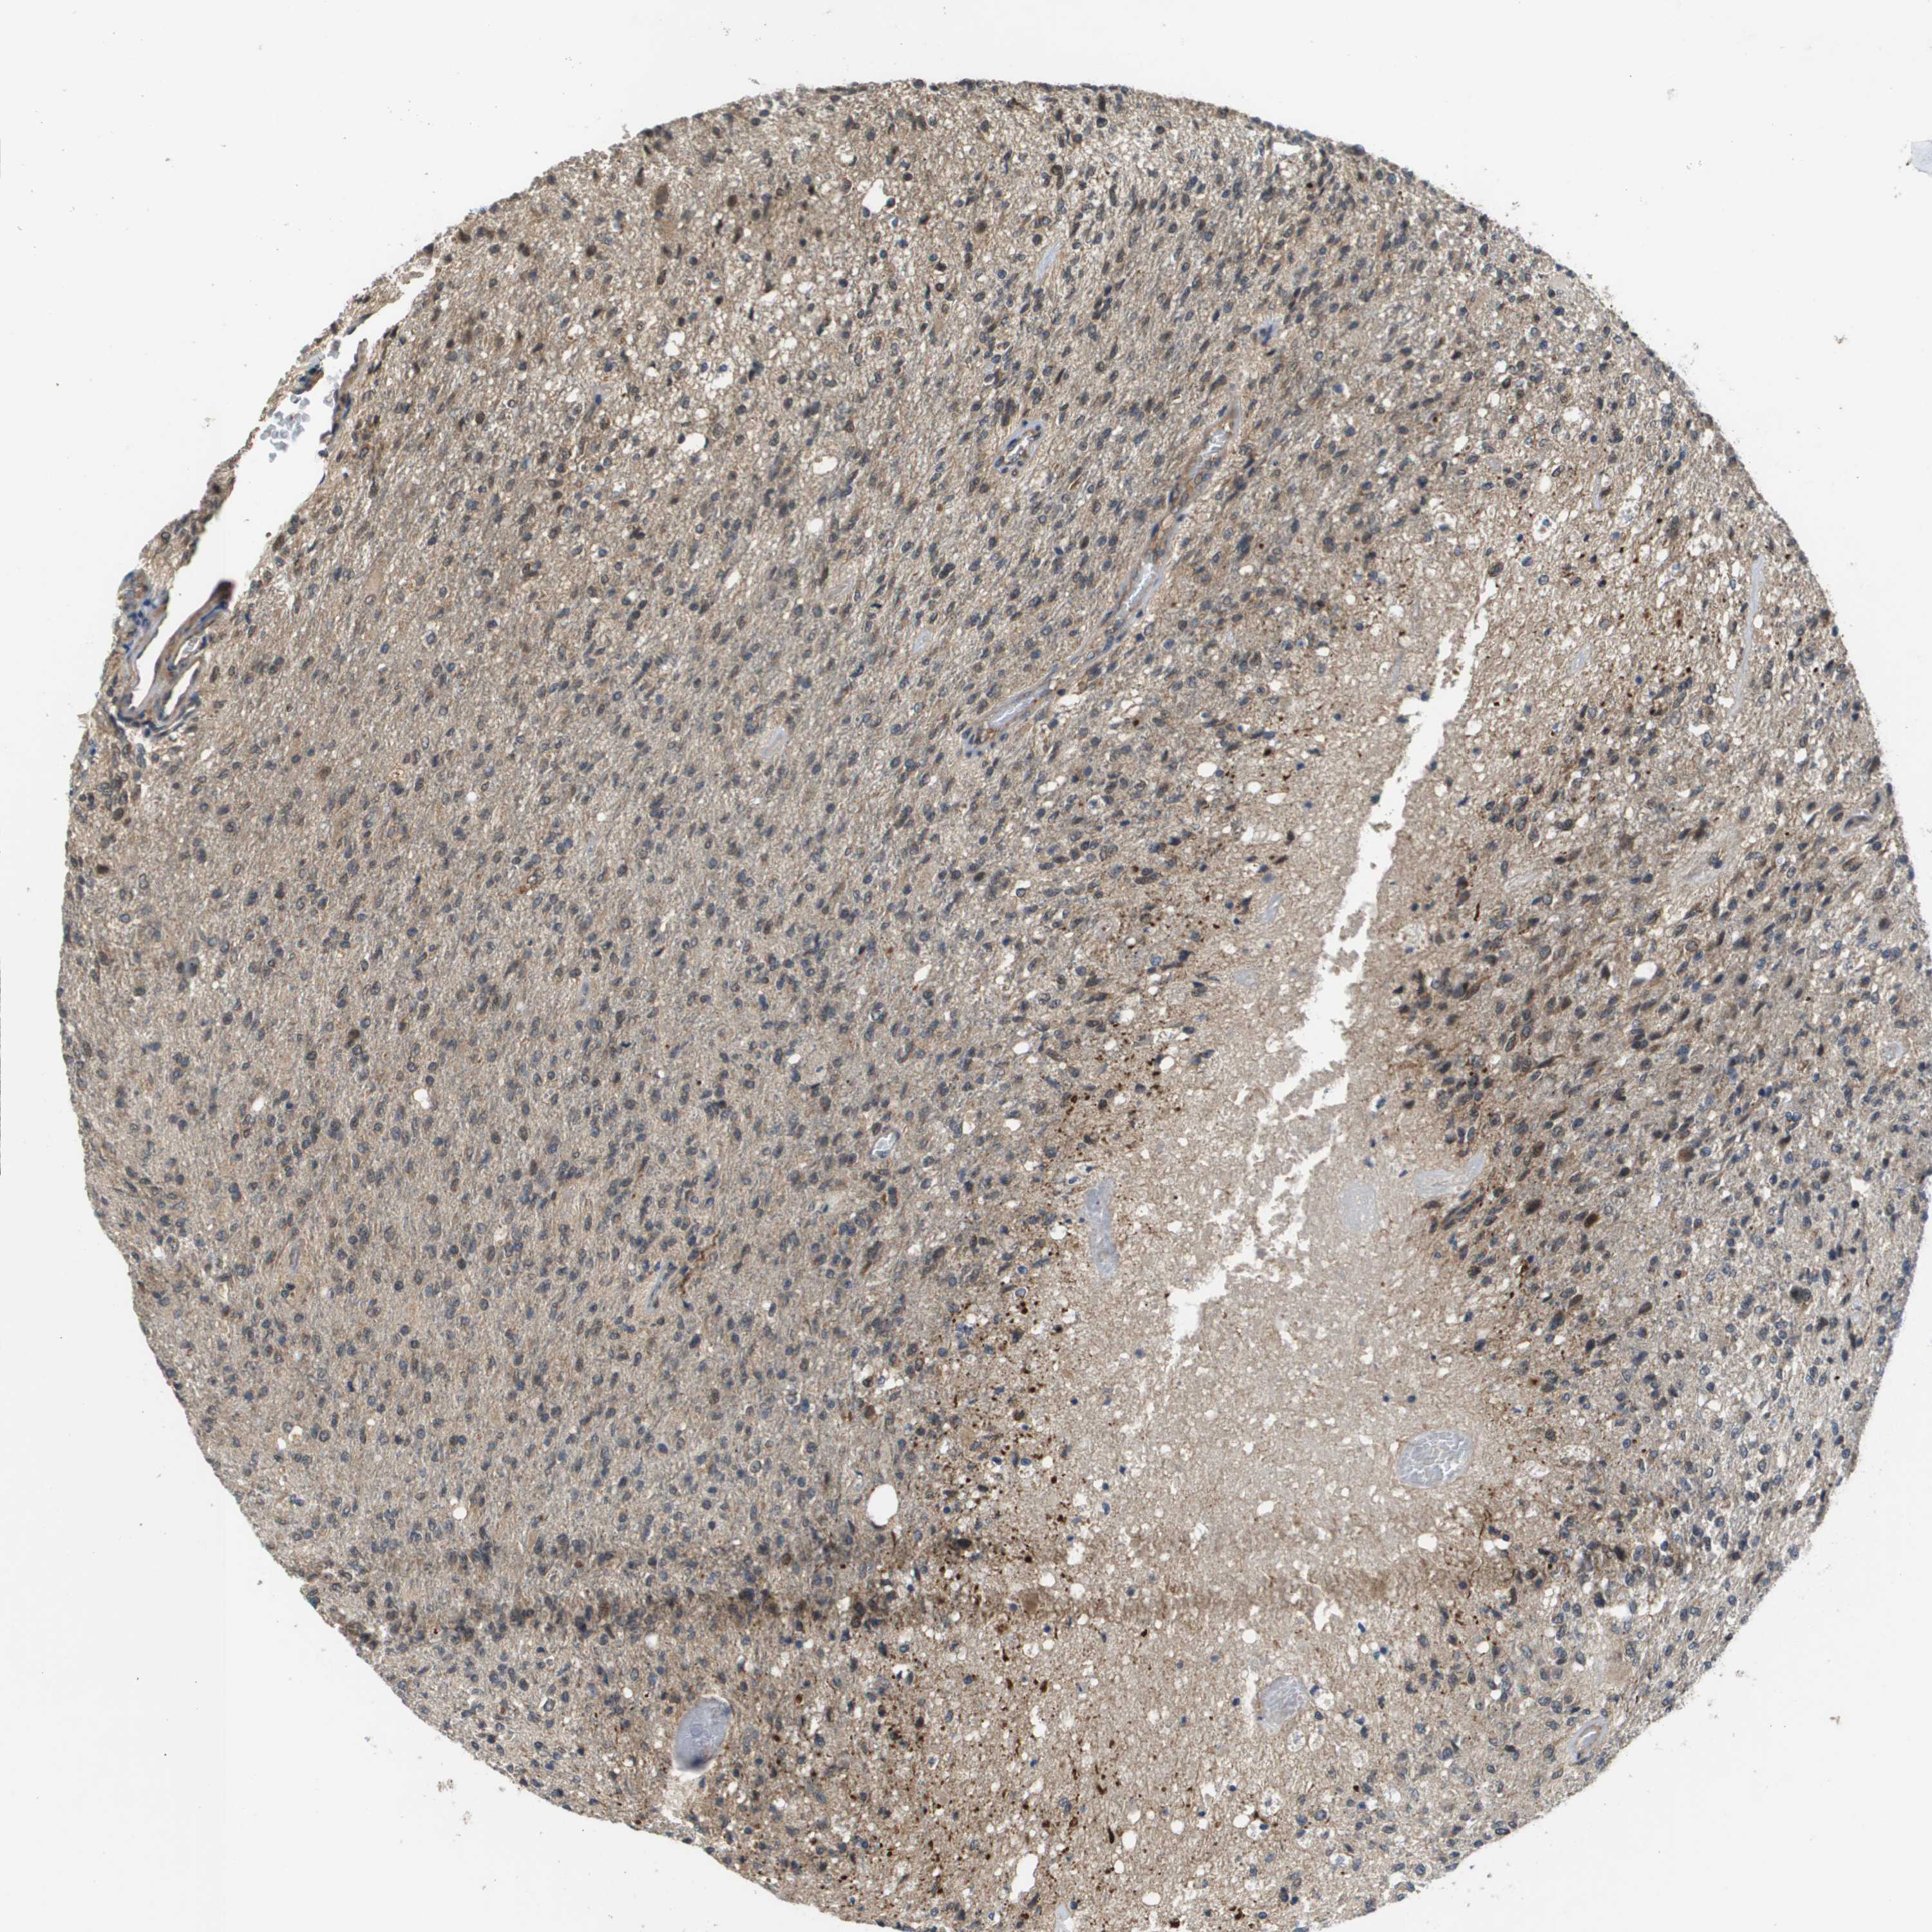

GLIOMA - Protein expressioni

A mouse-over function shows sample information and annotation data. Click on an image to view it in a full screen mode. Samples can be filtered based on level of antibody staining by selecting one or several of the following categories: high, medium, low and not detected. The assay and annotation is described here.

Note that samples used for immunohistochemistry by the Human Protein Atlas do not correspond to samples in the TCGA dataset.

Antibody stainingi

Antibody staining in the annotated cell types in the current human tissue is reported as not detected, low, medium, or high, based on conventional immunohistochemistry profiling in selected tissues. This score is based on the combination of the staining intensity and fraction of stained cells.

Each image is clickable and will lead to virtual microscopy that enables deeper exploration of all samples and also displays staining intensity scores, fraction scores and subcellular localization as well as patient and tissue information for each sample.

Antibody CAB017036

Staining

High

Medium

Low

Not detected

Intensity

Strong

Moderate

Weak

Negative

Quantity

>75%

75%-25%

<25%

None

Location

Nuclear

Cytoplasmic/membranous

Cytoplasmic/membranous,nuclear

Glioma, malignant, High grade

Glioma, malignant, Low grade